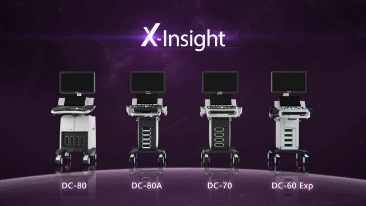

Diagnostisches Ultraschallsystem

DC-60 Exp

Ein vertrauensw├╝rdiger Allround-Partner

?bersicht

Als Allroundtalent meistert das DC-60 Expert mit X-Insight den klinischen Alltag in allen Aspekten und mit Leichtigkeit.?

Das eXklusive Design des Ger?tes, gepaart mit einer eXzellenten Bildqualit?t und einer eXtrem einfachen Bedienung, macht dieses diagnostische Ultraschallsystem zum verl?sslichen Partner in der Praxis.?